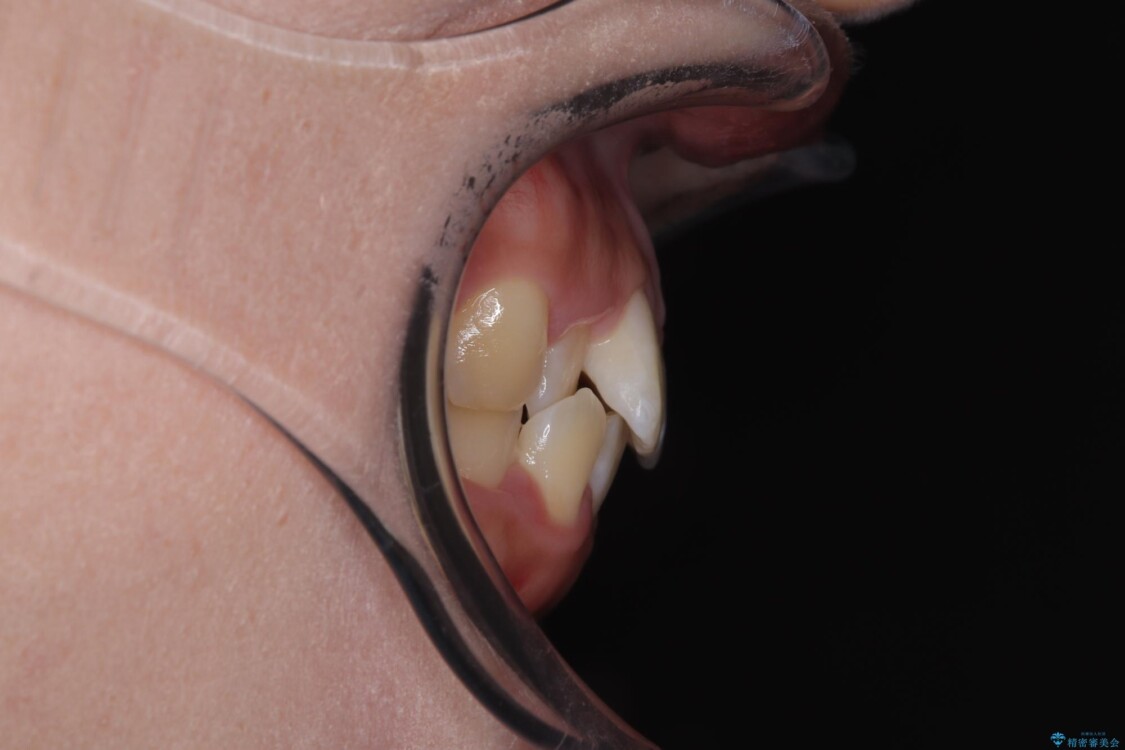

前歯のデコボコが気になるでのことで来院された患者様です。

歯列アーチが狭くスペース不足により前歯がデコボコしている状態でした。見た目を改善しつつ、前歯を前方に突出させず、自然な笑顔を目指したいというご希望でした。

治療前

• 目立ちにくい表側装置で1年完了!狭いアーチを側方拡大し前歯のデコボコを整えた症例 治療前画像